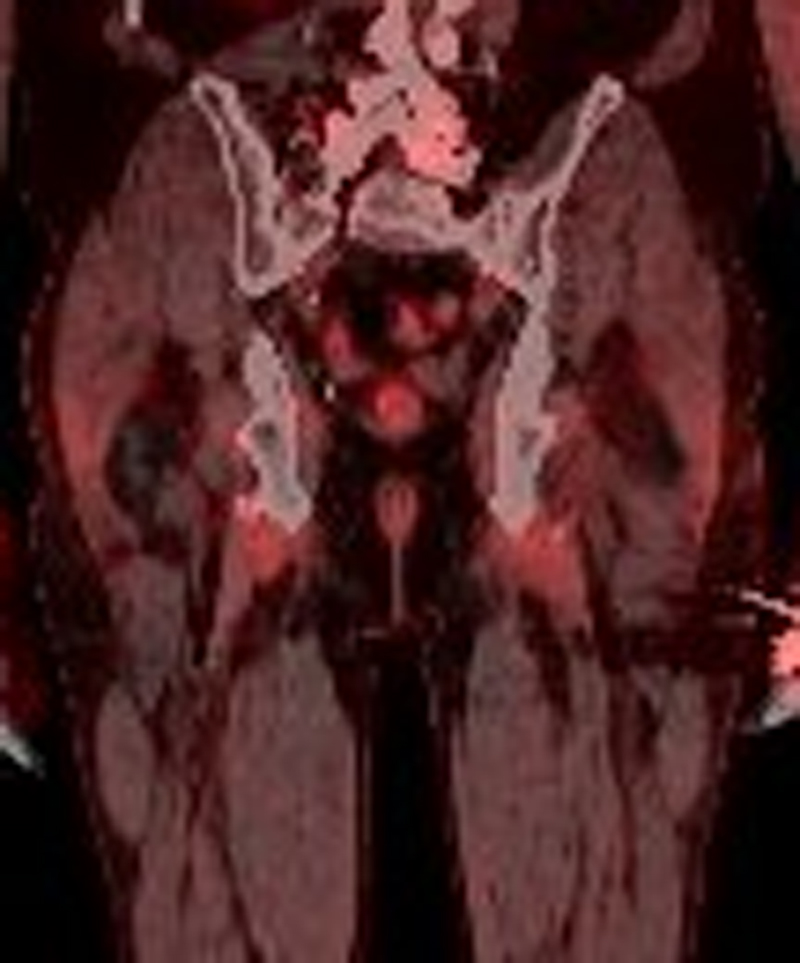

Over a period of one month, we observed slow but sustained improvement of the pain and a return to full mobility. PET-CT imaging for the melanoma follow-up 1, 13 and 15 months after the pelvic MRI did not show inflammatory activity in the area of the hamstring tendon insertion (figs 5 and 6). In the area of tendon insertion at the ischial tuberosity, there was a discrete elevation of fluorine-18-fluorodeoxyglucose (FDG) uptake, which could indicate a healing process. However, it also could indicate slightly elevated muscle tone. Because the patient reported no trauma or unusual physical activity, we considered medication as cause.

Figure 5 PET-CT of the pelvis 13 month after the rupture: coronary view.